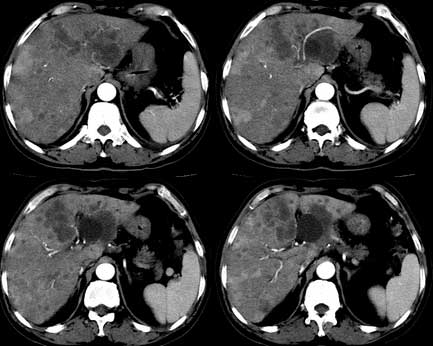

患者 男性 65岁,2005年8月行胆管癌切除术(切除胰头 胆囊及十二指肠),今行ct复查,请会诊,有没有复发?(近期患者发烧,重度黄疸)

考虑胆囊癌术后复发及肝转移,肝门区胆管扩张明显,左肾囊肿。

是单纯复发还是复发伴肝内转移?我个人认为应当再考虑一下,并倾向于后者。肝总管下端内、后侧见不规则软组织块影,部分侵入肝总管内。其边缘凸凹不平且模糊不清,渐进性不均匀强化。肝总管于此处管径突然变小,其上肝总管显著扩张,内见较均匀液性密度,管壁也很光整。肝内多发低密度病灶用复发引起的肝内胆管扩张显然不能解释的通,病灶分布与胆内胆管的走行不一致。而且随着时间的延续病变更加清晰,没有强化,部分还可见牛眼征。

肯定是:胆管复发并肝内广泛转移,还有肝及胆总管周围网膜炎性改变。腹腔干后第三层面腹膜后血管间结节状影,淋巴结肿大可能,这上面没法看清!

考虑复发并转移,肝门区胆管扩张,左肾多发囊肿可能.腹腔淋巴结转移.